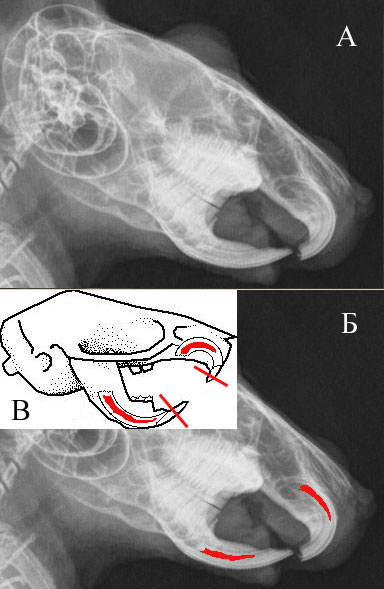

Строение резцов грызунов